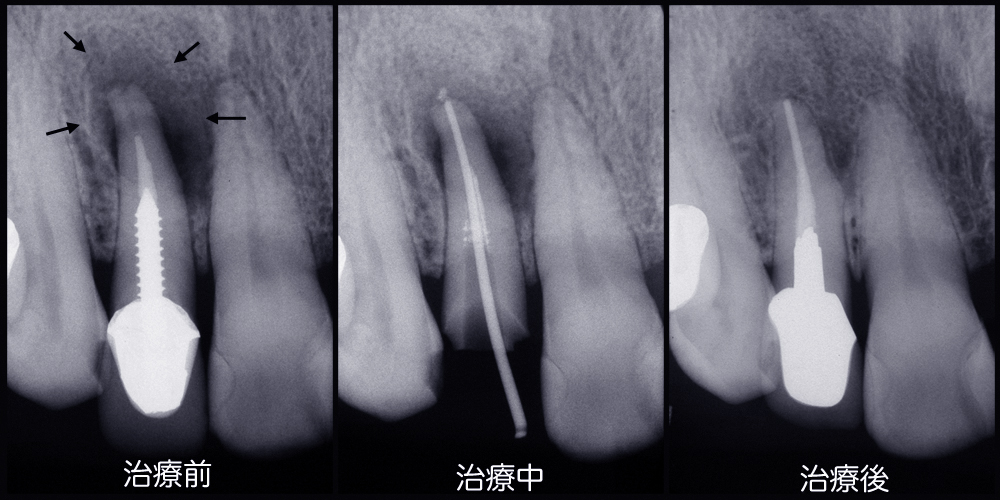

歯科医院でレントゲンを撮って説明を受けたことがあると思います。歯科のレントゲンフィルムは小さくてよくわからなかったという方が多いのではないでしょうか。レントゲンフィルムの種類や撮影法、現像法には多くの種類がありそれによって画像の鮮明度には差がでてきます。須貝歯科医院ではレントゲン診断にこだわり鮮明な画像が得られるようにシステムを整えています。また撮影されたレントゲンはパソコンのモニター上に拡大し、素人の患者さんが見てもわかるようしています。

上のレントゲンでは根の先端に大きな病巣があるのがわかります。右側が治療後ですが病巣が消えています。歯を入れるだけでなくレントゲンで骨の状態の改善が確認できなければ本当に治ったとは言えません。

一見何でもなさそうですがレントゲンでは大きな虫歯が確認できます。鮮明なレントゲンであれば素人の患者さんにも虫歯であることがわかります。